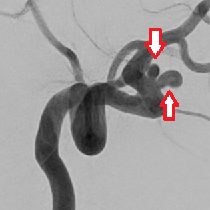

脳動脈瘤

脳動脈瘤(脳内の動脈にできた膨らみ)の破裂により、脳脊髄液のある脳の表面のくも膜下腔に血液が流れ出てくも膜下出血が発症します。典型的には、ハンマーで殴られたような激しい頭痛で発症し、多くの場合嘔吐を伴います。また意識低下で発症することもあります。

外科的治療では、開頭して脳動脈瘤の頸部を金属製のクリップで閉塞するクリッピング術が行われます。脳血管内治療では予防的に、血管を通して未破裂脳動脈瘤内に到達し、プラチナ製のコイルを動脈瘤に詰めるコイル塞栓術が行われます。年齢、全身状態、脳動脈瘤の形態から、より安全で確実な治療手段を選択しています。

(下図)双こぶ状の脳動脈瘤に対してステント(金網でできた筒)を併用してコイル塞栓術を施行しました。動脈瘤は完全に閉塞しています。